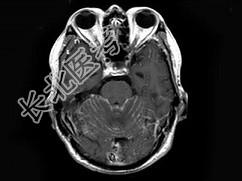

- 单项选择题男,55岁, 头痛40余天,呕吐2天伴共济失调。化验检查: 脑脊液蛋白:2006mg/l, 细胞数60个/mm3MRI平扫显示不佳,增强扫描后见脑膜强化及脑内小结节状强化以脑膜强化为明显, 据此最可能的诊断为 ( )